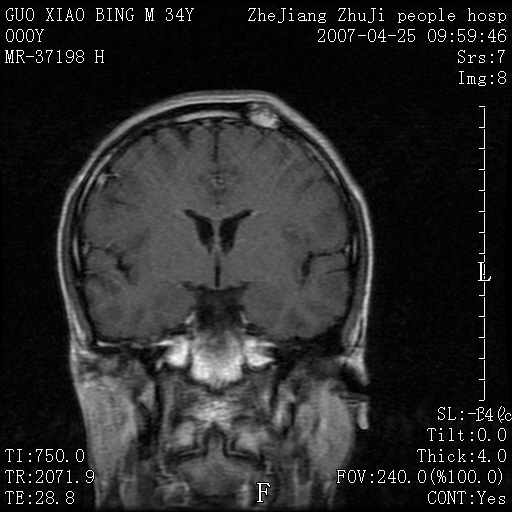

以下是引用qiuleiyu在2007-4-27 16:41:00的发言:[br]ct左侧额顶部囊性膨胀性骨质破坏,边缘有轻度硬化,其内示多发点条状高密度。[br]mri;t1低信号,t2明显高信号。界清。增强后明显强化。[br]综合考虑;颅内血管瘤。上传该病例,目的在于加深印象,共同学习。[br]骨血管瘤好发于颅骨及椎体。为良性肿瘤。组织学上分海锦型及毛细血管型。前者多见。[br]颅血管瘤典型影像学表现;[br]1,平片;类圆形骨质破坏,边缘硬化,内示中央向周边年轮状辐射(残存增粗骨小梁)。[br]2,ct;颅内板障内膨胀骨质破坏,边缘硬化,内示密集点状及放射状骨针影。[br]3,mr;t1、t2高信号。该病例t1不高可能与血流较丰富有关。边缘低信号。增强明显强化。[br]鉴别;[br]1,脑膜瘤;主要累及内板,与血管瘤发生于板障不同。颅板骨质增生硬化,与颅内垂直放射状骨针。与血管瘤日光放射状不同。增强可见脑膜尾征。[br]2,嗜酸性肉芽肿;起自板障溶骨性骨质破坏。内无点状及放射状高密度影。边缘硬化不明显。局部可有骨膜反应。[br]3,转移性肿瘤;溶骨破坏边缘模糊,无硬化边。发展迅速。有原发肿瘤史。可多发。可出现软组织块。[br]4,单发骨髓瘤;发病年龄较大,临床可能全身骨质疏松,骨痛。免疫球蛋白增高。部分病例本周氏蛋白可增高。可有边缘硬化,然内无点状高密度影。[br]